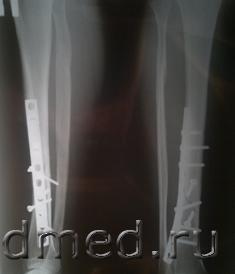

уважаемые эксперты помогите разобраться, я получил перелом правой голени. причина перелома такова:на ровном поле сначала меня ударили в голень ботинком, а после мне наступили на правую ногу и удерживая стопу своей ногой человек положил меня на левый бок. Врач делавший операцию выставил клинический диагноз-ОТКРЫТЫЙ перелом обеих костей правой голени со смещением отломков кзади и наличие раны средней трети передней части голени. Однако после операции через 2 месяца было сделано новое заключение судмедэксперта в котором подробно описан диагноз- ЗАКРЫТЫЙ оскольчатый косой перелом обеих костей правой голени,малой в верхней трети и большеберцовой в нижней трети диафиза со смещением дистального отломка кзади , а так же рана передней поверхности средней трети правой голени размером 0,1 на 0,1 см. у меня несколько вопросов 1/ можно ли эти диагнозы считать противоречивыми,ведь у меня поломано 2 кости одна из которых малая имела закрытый перелом а большая открытый? 2/ могли ли образоваться эти переломы один от удара ботинком другой от падения? 3/ мог ли я с такой травмой свободно передвигаться без посторонней помощи 4/ мог ли такой перелом образоваться от дтп за рулем в машине при небольшом лобовом ударе.

2.Для этого нужно исследовать все рентгенограммы (особенно - первичные), а не только одну из многих рентгенограмм, которую вы посчитали возможным выложить.